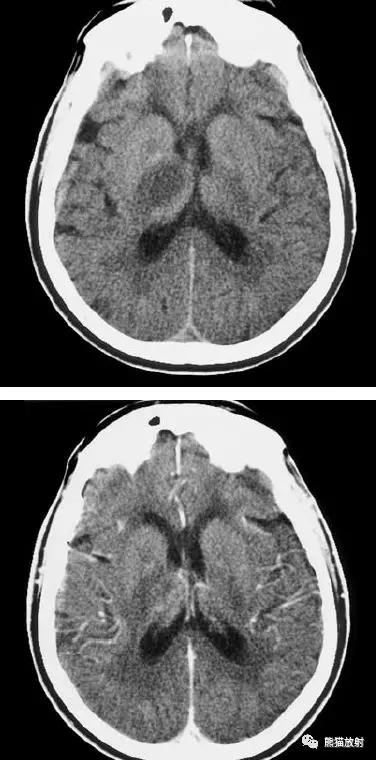

右侧大脑中动脉区域梗死的典型演变:

a)急性期

b)早期亚急性期(2天,从临床起病开始)

c)亚急性晚期(2周后)

d)慢性期(一年后)